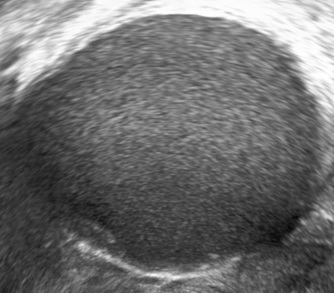

Ultrasound findings

- Frequently large, unilateral, cystic mass.

- Usually multilocular.

- Smooth walls.

- Contains small cystic components or honeycomb-like loculi.

- Intralocular fluid of varying echogenicity.

- Linear calcifications (rare).

- Papillary projections (rare).

- Mucinous ascites may present after cyst rupture.